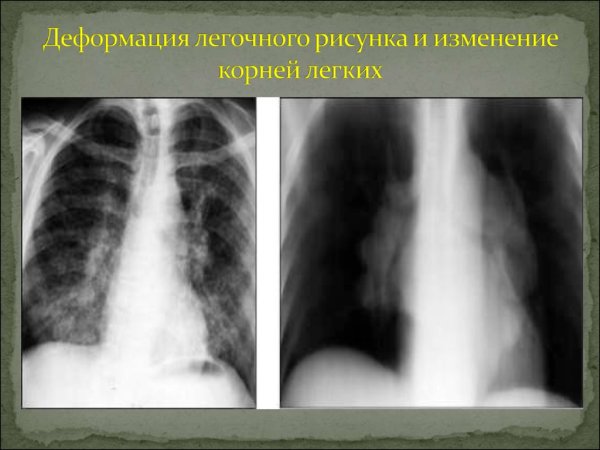

Деформация легочного рисунка

Деформация легочного рисунка на рентгене

Деформация корней легочного рисунка